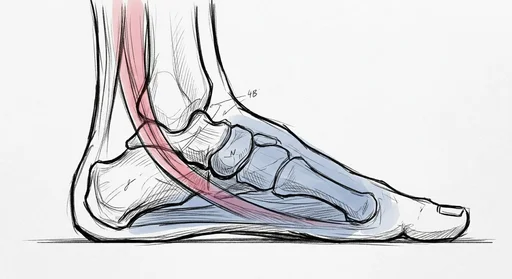

Heel & Arch

Achilles & Calf